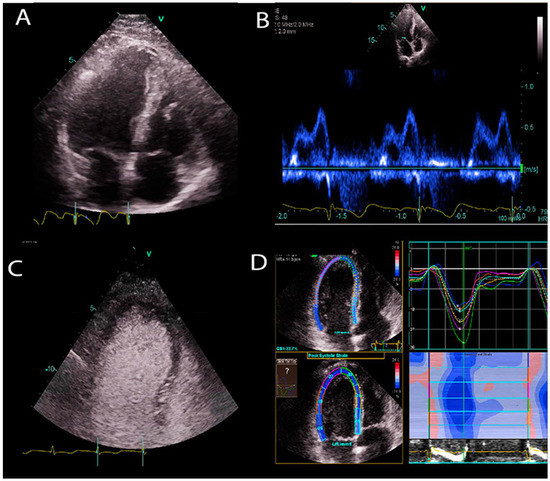

1.1. Transthoracic Echocardiogram

2.2. Image Segmentation and Quantification

2.3. Disease Diagnosis